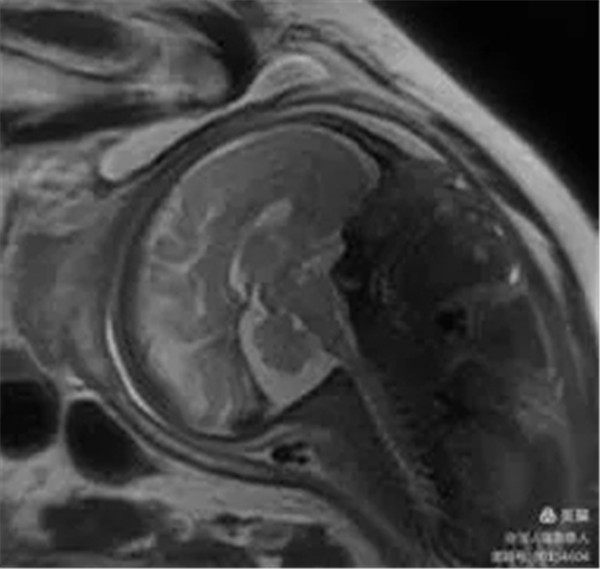

2、胎儿颅脑磁共振成像

病例12:评估胎儿颅脑发育情况。

图6,矢状位T2WI-显示胎儿颅脑